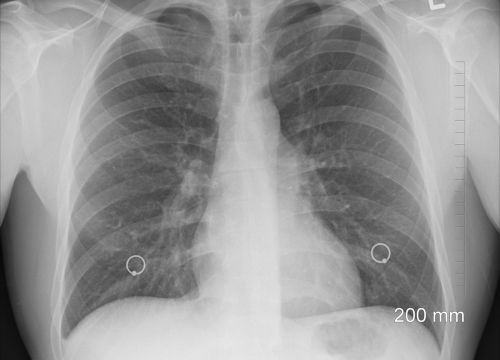

KOPB

U Hrvatskoj 1700 smrtnih slučajeva godišnje zbog plućnih bolesti